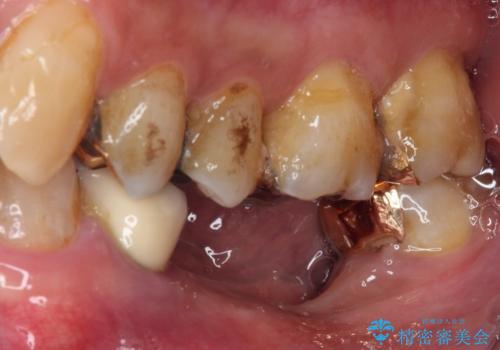

- 下顎両側の欠損と上顎前歯のデコボコを気にして来院された患者様です。

奥歯に欠損が多く、矯正治療はやや難航することが予想されますが、患者様の希望もあり、上顎左右小臼歯を1本ずつ抜歯し、ワイヤー装置にて矯正治療を行うこととしました。

矯正歯科治療を行うに当たり、痛みや違和感を感じている歯の根管治療を行い、矯正治療中にインプラント埋入し、補綴治療と矯正治療を同時に終了できるように進めて行くこととしました。

銀歯やむし歯治療されている歯を抜歯する治療計画としたため、やや時間はかかりましたが、治療後の仕上がりには大変満足していただけました。